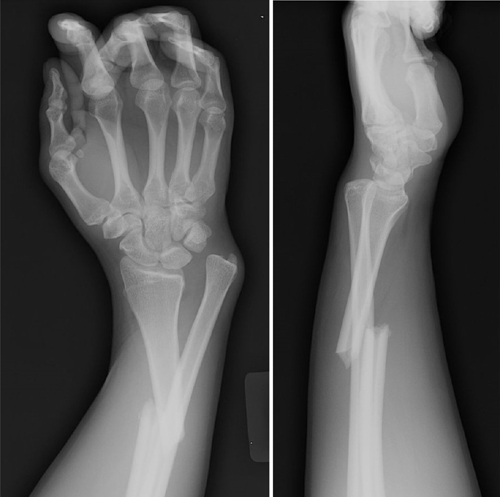

Apakah Patah Tulang? Patah tulang adalah kondisi terputusnya keutuhan susunan tulang pada tubuh ....